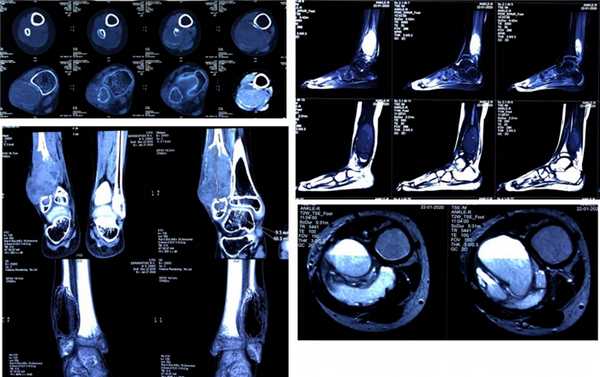

В нашей клинике в стандарт обследования пациентов с подозрением на наличие аневризмальной кисты кости входят рентгенография и компьютерная томография.

Рентгенологически различают два типа аневризмальной кисты - расположенные центрально и эксцентрически. В течение аневризмальных кист выделяют три фазы - остеолиза, отграничения и восстановления.

КТ позволяет выявить характерный для аневризмальной кисты симптом “горизонтальных уровней”, а также относительную плотность для уточнения тактики лечения.

Диагностика заболевания начинается с осмотра ортопедом-травматологом или неврологом. Иногда в ходе него удается пальпировать выпячивание на поверхности кости, а также обнаружить симптомы неврологических нарушений. Но основным методом диагностики является рентген. На полученных снимках можно заметить эксцентрический литический очаг, нередко выходящий за нормальные размеры кости. Дополнительно обнаруживается присутствие характерного склеротического ореола. Сама киста визуализируется в виде многокамерного образования со структурой по типу мыльных пузырей.

Дополнительно для подтверждения диагноза и оценки состояния межпозвонковых дисков, спинного мозга, мягкотканых структур пациентам может назначаться МРТ. Комплекс этих исследований позволяет правильно оценить степень агрессивности костной кисты позвоночника, а также разработать оптимальную тактику лечения.